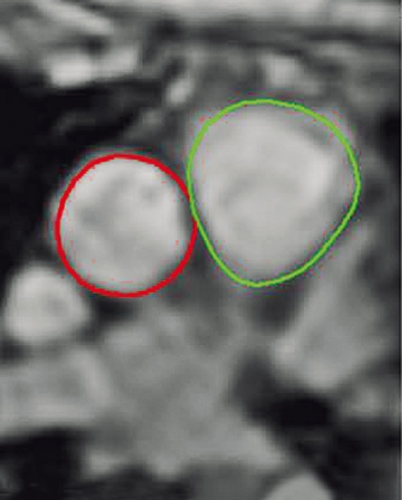

Faskontrast-MR används vid många svenska sjukhus främst för att kvantifiera flöden vid intrakardiella shuntar och klaffläckage (Figur 1) men också för angiografi utan användning av externt kontrastmedel [13, 14]. Vid shuntkvantifiering bedöms i regel förhållandet mellan volymflödet i lungcirkulationen (lungartären) och i systemcirkulationen (uppåtstigande aorta).

Faskontrast-MR möjliggör noggrann bestämning av volymflöden. Flödet beräknas utifrån blodkärlets area och hastigheten i varje bildelement (dvs hänsyn tas till flödesprofilen över kärlets tvärsnitt) och summeras över ett hjärtslag. Dessa hastighetsdata kan mätas med hög noggrannhet jämfört med de syremättnadsvärden som är basen för kateterberäknad minutvolym och shuntflöde [15]. Noggrannheten i flödesdata kan och bör kontrollmätas med hjälp av flödesfantom.